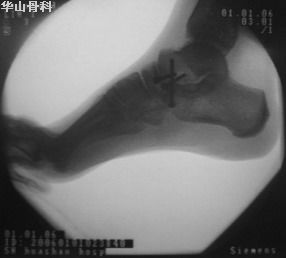

距骨骨折--CT若為距骨後突骨折,除踝關節後部壓痛外,足呈蹠屈狀,踝關節背伸蹠屈均可使疼痛加重;若為縱形劈裂骨折,踝關節腫脹嚴重或有大片瘀血斑,呈內翻狀畸形;可在踝關節內側或外下側觸到移位的骨塊突起。

由於跟骨及踝部骨折可與距骨骨折同時發生,有時臨床鑑別是困難的,多需X線檢查確診。但距骨後突骨折,對經驗較少的醫生容易與距骨後大小相似的副骨相混淆,後者是一邊緣光滑的子骨,同時距骨後緣也無缺損現象,而距骨後突骨折則相反,應注意鑑別。